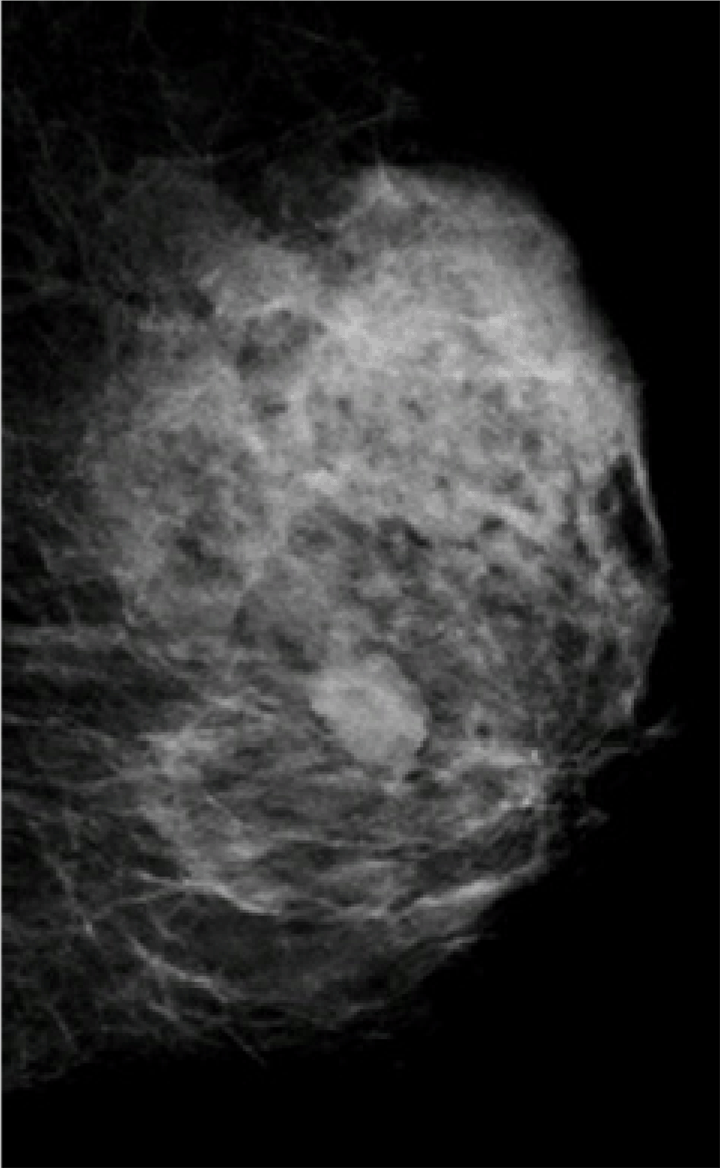

On admission, physical examination revealed a 2.0x2.0 cm palpable nodule which was elastically firm and mobile in the upper external quadrant of the left breast with no associated skin findings. There was no axillary or supraclavicular lymphadenopathy, and no abnormal nipple discharge. Mammography showed a 2.0 cm in diameter high-density shadow lesion, which corresponded to the palpable mass, with partly ill-defined margins and without specula or microcalcification. (Figure 2) An ultrasonography of the left breast revealed a hypoechoic and relatively irregularly shaped mass with an ill-defined margin. (Figure 3) A core needle biopsy of the lesion showed fibrosis and a small granulomatous lesion infiltrated by lymphocytes and foamy histiocytes, and there was no evidence of malignancy. From the physical examination, CT scan, ultrasonographic findings, a diagnosis of breast cancer could not be ruled out, and an excisional biopsy was also done when the sigmoidectomy was performed.

Figure 2: Mammography showing a 2.0 cm in diameter high-density shadow lesion, which corresponded to the palpable mass, with partly ill-defined margins and without specula or microcalcification.